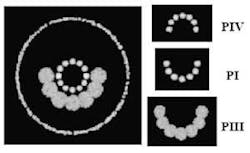

Pablo Artal and Juan Tabernero at the University of Murcia (Murcia, Spain) have built a prototype imaging system for recording reflections (called Purkinje images) from four ocular interfaces-air-cornea (PI), cornea-aqueous (PII), aqueous-lens (PIII), and lens-vitreous (PIV)-in vivo. The prototype imaging system contains a chin and forehead rest for the subject; a semicircular array of infrared LEDs to illuminate the eye; a telecentric camera objective and CCD camera to collect and record the reflections; an array of LEDs for the subject to fixate on; and other optical components.

When an illumination source is aligned with principle line of sight in a well-aligned human eye, the reflection images align around a common center. PI and PII usually overlap due to small corneal thickness. PIII appears largest, and PIV appears inverted. The outermost circle, in the large image on the left of well-aligned reflections, traces the circumference of the pupil. The relative positioning of the Purkinje images changes, however, with misalignments, either among ocular surfaces or between the illumination source and the line of sight. The new instrument is expected to prove useful in basic studies of the eye and in clinical ophthalmology. Contact Pablo Artal at [email protected].